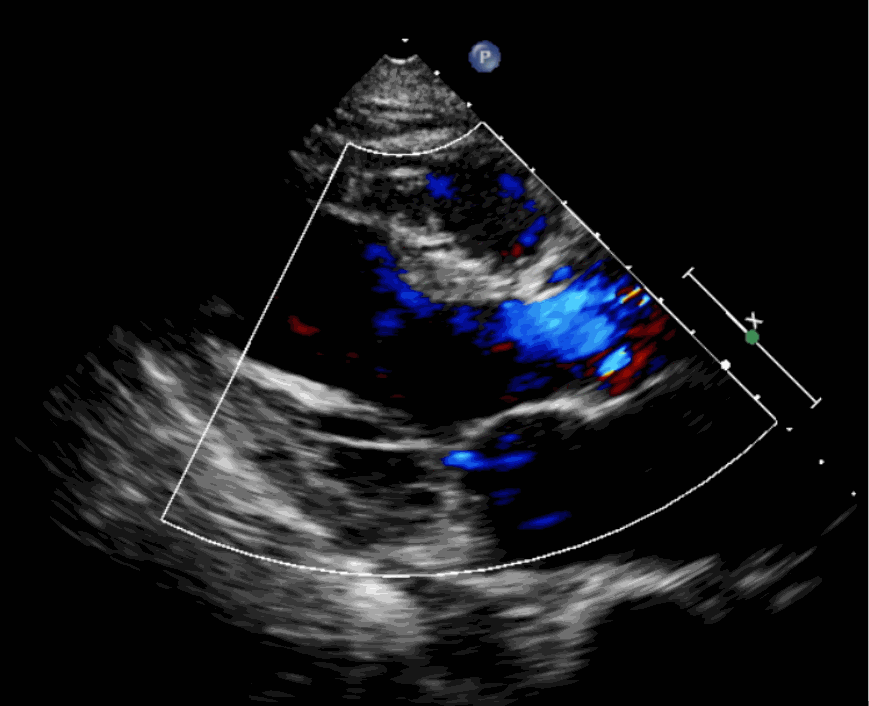

術前超聲影像圖

該例患者為62歲,女性,因“間歇性心悸、胸悶、氣短、胸痛1年,加重1周”之主訴入院。入院診斷:主動脈瓣重度關閉不全,二尖瓣、三尖瓣輕度關閉不全,心功能III級;冠狀動脈粥樣硬化性心臟病。行心臟超聲心動圖提示“主動脈瓣重度關閉不全;瓣口水平以下左室下壁、后下壁搏幅減低;EF值 0.30,左房、左室大、右房大小正常高限;二尖瓣、三尖瓣關閉不全;輕度肺動脈高壓(收縮壓42mmHg);主動脈硬化;左室收縮功能重度減低。經心血管外科劉洋、楊劍教授、麻醉科陳敏教授及超聲科孟欣教授等專家團隊綜合評估,判定患者為外科手術高危患者。